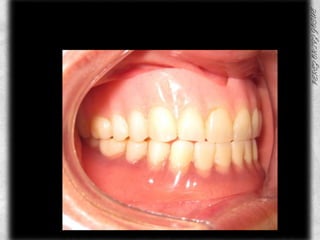

ANTECESDENTES PROSTODONTICOSPROSTODONCIA SUPERIOR CON 7 AÑOS DE USO Y DESGASTES EN TODOS LOS DIENTES, SIN PRESENCIA DE SARRO Y CON MOVILIDAD

PROSTODONCIA DEL PACIENTE INFERIORPROSTODONCIA INFERIOR CON BUENA ANATOMIA OCLUSAL EN LOS MOLARESCON 6 MESES DE USOBUEN SELLADO, SOLO SE HIZO LA INFERIOR

ANTERIOR DE PROSTODONCIADOS COLORES DIFERENTES DE ACRILICOSANTIESTETICA